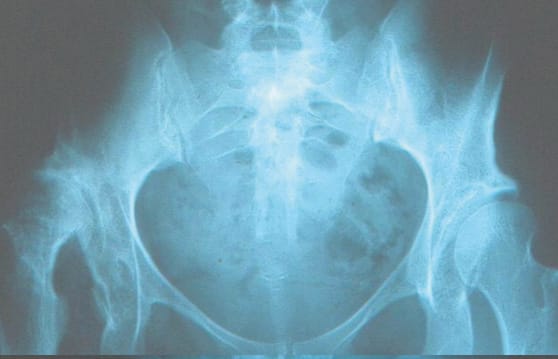

This strategy usually begins with the Smith–Petersen approach and a single osteotomy incision above the acetabulum, oriented cranially from the outside inwards under fluoroscopic guidance, and following the contour of the femoral head. At the planning stage, it is important to make sure that the osteotomy will end below the sacroiliac joint, or it will not be possible to mobilise the distal fragment. The new positioning is achieved by placement in abduction and fixation with a 6.5mm screw. The main complications described, though certainly rare, are nerve damage (sciatic nerve) and non-union. Functional outcomes are good, with survivorship over 70% after 15 years (74–97%), 60–85.9% after 30 years and 35% survivorship after 40 years in Chiari’s original series. This technique is not especially sensitive to deformity of the femoral head, subluxation or osteoarthritis if dysplasia is severe with negative VCE and VCA (< 0°) (Figure 8).

In DDH without subluxation and/or with repositioning on the abduction image and no osteoarthritis, the best choice is acetabular reorientation, as long as this procedure has been mastered, the hip is mobile and congruence is improved on imaging of repositioning. Since RAO has only been validated in Asian populations, we perform PAO as this has the benefit of a less invasive approach. However, when a hip is non-congruent this technique is contraindicated (unless it is combined with an osteotomy to reduce the femoral head, a technically complicated and risky procedure) so the choice will be between a Chiari osteotomy and bone block. The Chiari osteotomy is undoubtedly more difficult but it gives better results in the long term, and this is why we prefer it (Figure 10). It is also less sensitive than bone blocks to osteoarthritis and subluxation, in cases of severe dysplasia. Bone block is the more straightforward technique but it is less effective when there is osteoarthritis and/or subluxation, so its indications have greater overlap with PAO and RAO. In patients with moderate acetabular dysplasia, excess anteversion and valgus femur, our strategy is firstly a femoral varising derotation osteotomy, associated with a step to address the acetabulum if necessary, once the more straightforward femoral step has been completed.